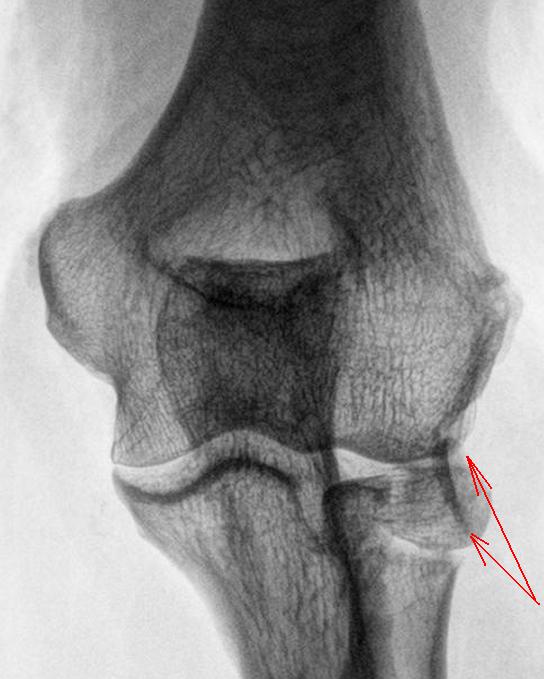

Хотелось-бы услышать мнение коллег и коллеги Вега, по поводу, помеченного красными стрелками, и откуда "это" оторвалось и что это за штука. Мне до конца субстрат данного тенеобразования не понятен.

Да, прекрасно виден субкапитальный перелом лучевой кости, с распространением линии перелома на суставную поверхность головки. Но что с локтевым отростком локтевой кости. Что с контуром локтевого отростка, помеченного зелеными стрелками, он довольно плохо дифференцируется, на мой взгляд там и "ступенька" намечается? Или "игра теней"?

А что это за дополнительная тень на фоне локтевого отростка? На мой вгляд, чтобы с ней разобраться, надо произвести рентгенографию локтевого сустава в "косых проекциях".

На мой взгляд, боковая проекция, еще более "интересная", чем "прямая". Понятно, что "изменения" - желтые стрелки имеют отношение к лучевой кости, а вот к "чему" имеют отношение "изменения" в теневой картине, помеченные "красными" стрелками?

Уважаемые коллеги! Перелом, без сомнения, довольно редкий. На мой взгляд имеется внутрисуставной перелом головки лучевой кости с ротацией отломка суставной поверхностью кнаружи на 90 градусов. В таких случаях меня всегда, в первую очередь, интересует механизм травмы, приложение повреждающей силы. С локтевым отростком думаю все в порядке.

Что касается фрагмента суставной поверхности головки луча, отмеченного красными стрелками - как откроем сустав, так и будет видно: если встанет на место и нормально удержится - оставим, если нет - удалим. И зафиксируем основной отломок шурупом.